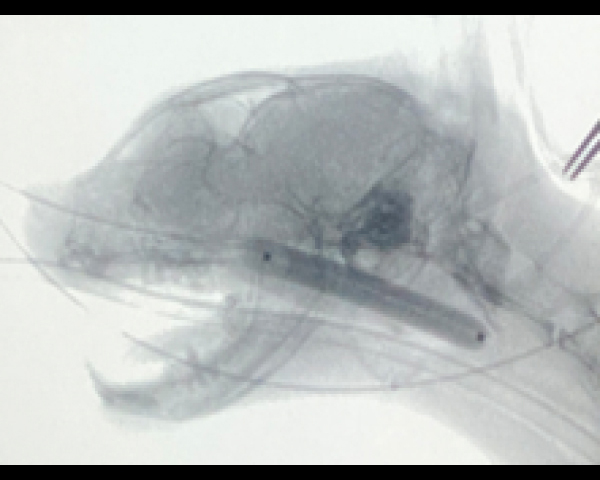

Cアームを用いたバルーン拡張術